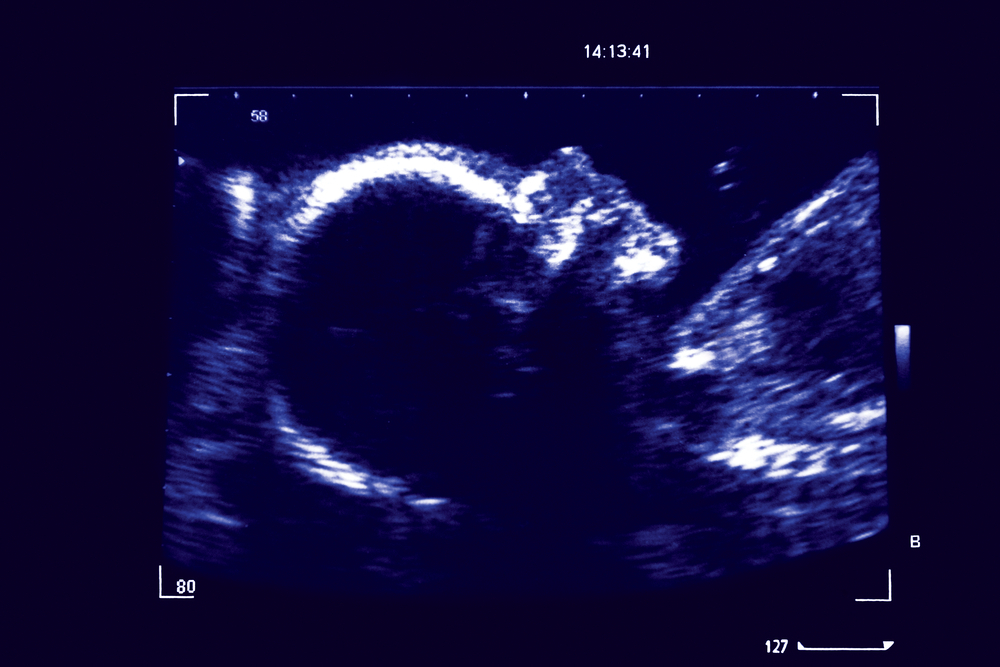

There are various reasons why an ultrasound scan is required in the 6th week of pregnancy, includingEarly pregnancy scan ultrasound 5 weeks gestation ultrasound appearances of a pregnancy at 5 weeks gestation ultrasound appearances of a pregnancy at 5 weeks gestation11/3/ · At 5 weeks into pregnancy things are so small there is very little to see on ultrasound Even at 6 weeks it can be difficult to see an embryo with some people The image above shows a 5 week pregnancy, but it won't always be this clear for all people

5 weeks pregnant baby size scan-8//18 · The ultrasound scan during fifth week of pregnancy is consistent part of the process that one needs to go through The ultrasound scan will help you to give a confirmation of your pregnancy and your embryo's condition thereby, this is just the beginning to your journey of being a mommy!Somewhere between 4 and 5 weeks, we can sometimes see a small black fluid area in the uterus but we cannot confirm it is a pregnancy sac until we can see something growing inside it